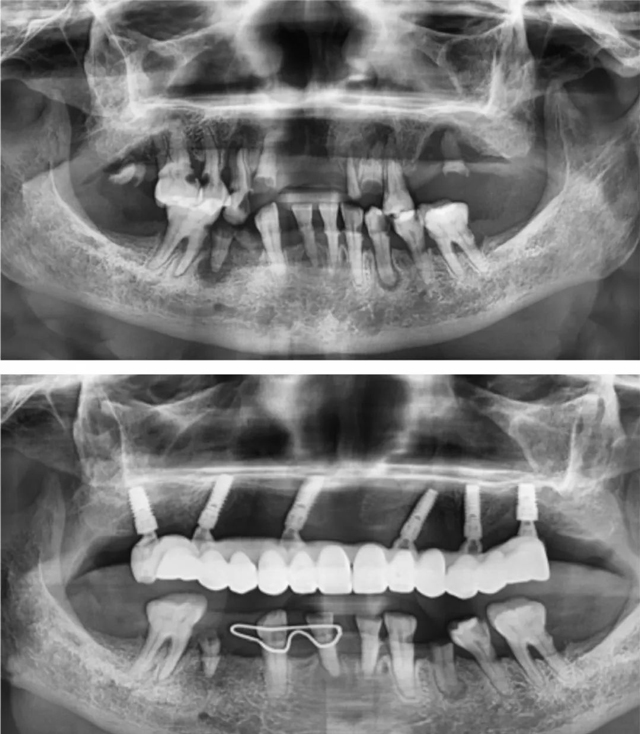

患者术前术后全景片

曾经,一位八十多岁的阿姨,其上牙全是烂牙根,由于就医不便,牙齿问题一直被搁置。韩沛接诊后发现,阿姨骨量极差,骨头很薄,进行半口种植手术存在一定难度。面对复杂的牙齿状况和听不懂的专业术语,阿姨和家属有些慌张与迷茫。

韩沛没有丝毫的不耐烦,与阿姨及其家属进行了多轮耐心细致的沟通,将每一项风险都清晰明确地告知,用通俗易懂的方式讲解有关半口种植的情况,还结合阿姨的自身情况给出了科学合理的应对方案。阿姨和家属被韩沛的专业与负责深深打动,对于手术也不再紧张,最终决定接受手术。

在患者和家属的高度信任下,手术得以顺利开展。术后,阿姨十分满意,生活质量得到了极大提升,她逢人便夸这位韩医生医术高超、耐心又有亲和力。